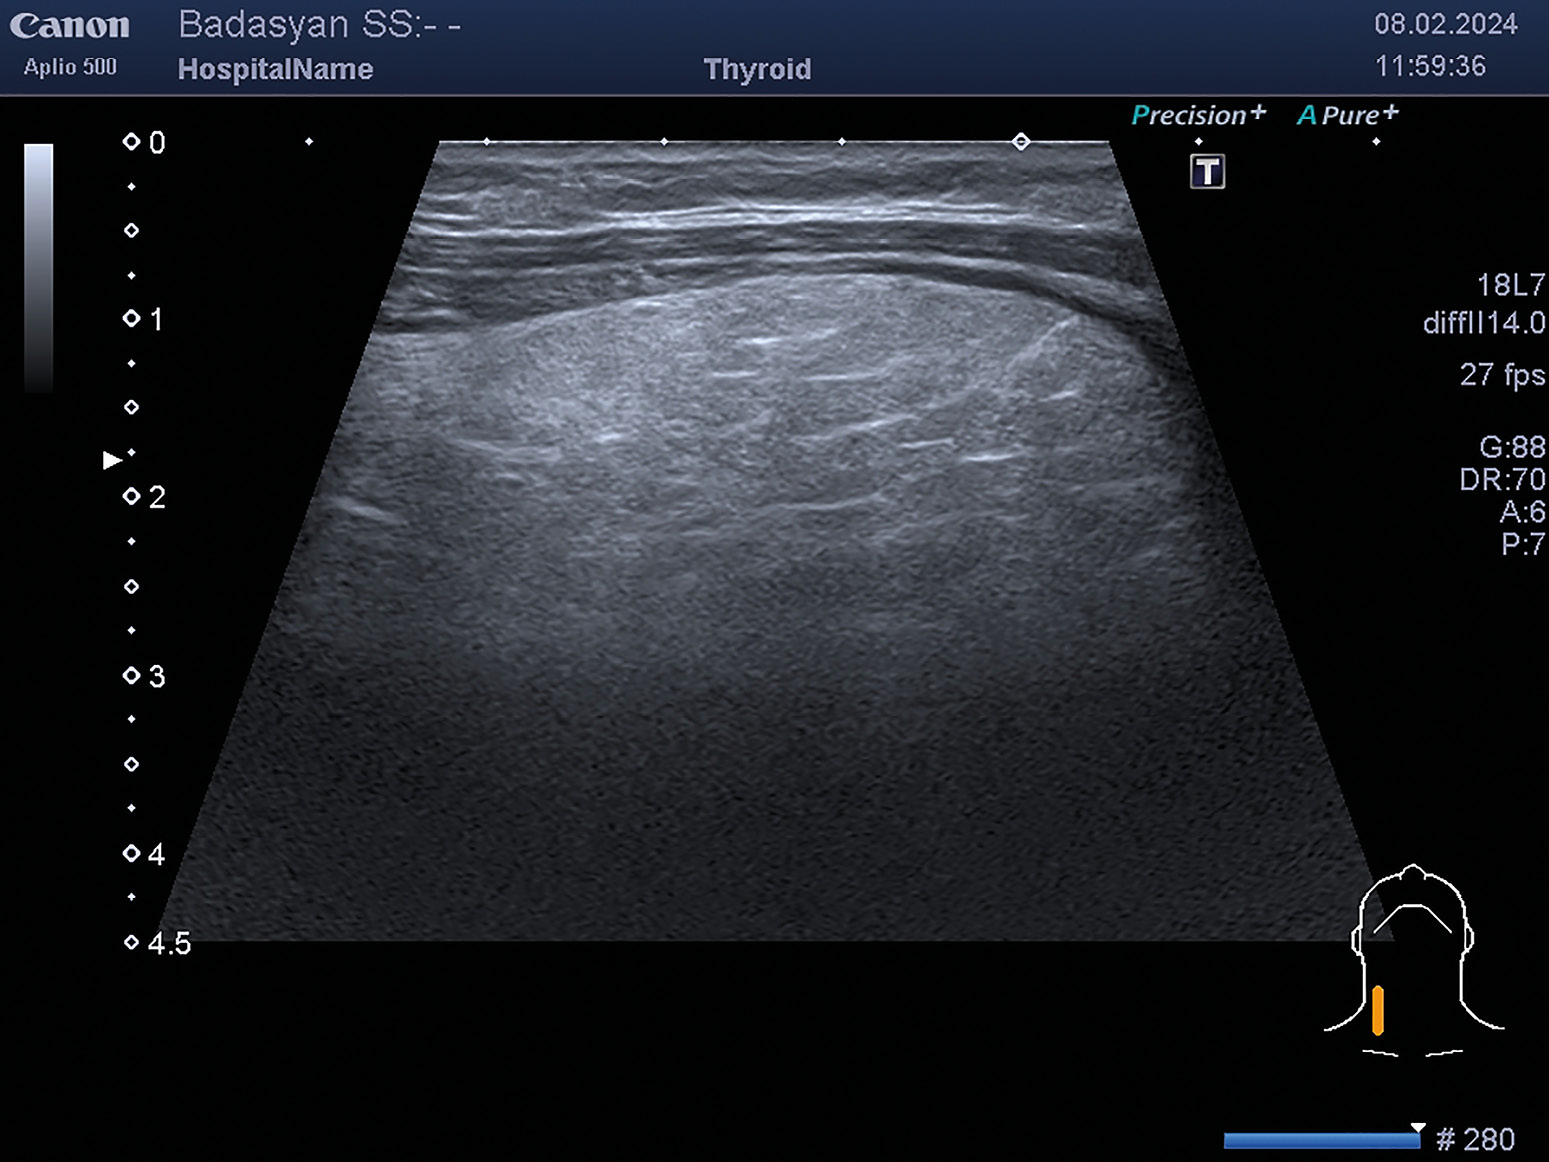

1. Рисунок 1. УЗИ щитовидной железы.

Тема

Тип Исследовательские инструменты

Посмотреть (221KB)

Метаданные ▾